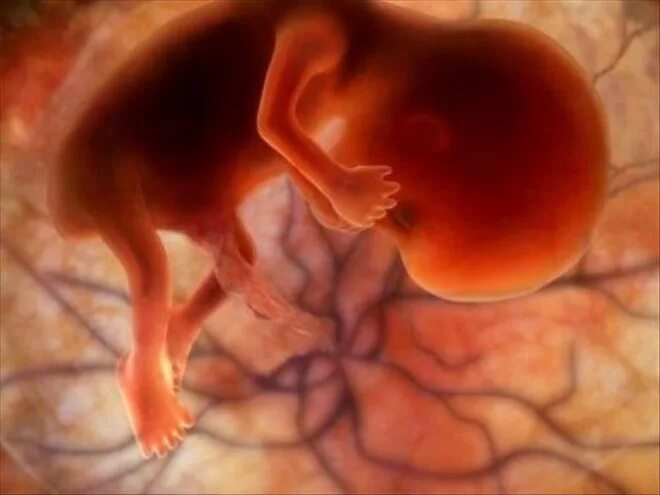

11 недель ощущения